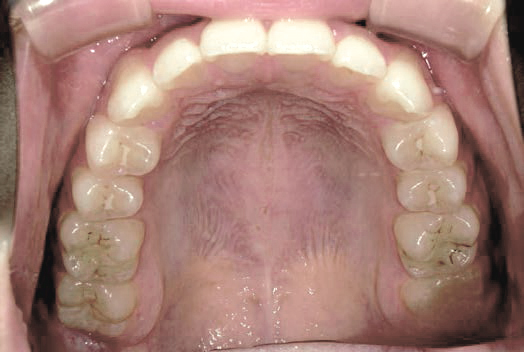

Before

上あごの成長が少なく、特に前歯のガタガタが目立っていました。口呼吸のクセや飲み込み方に良くないクセが確認されました。

治療を終えて

マイオブレイスとBB1装置で上あごの成長を助け、鼻呼吸や正しい飲み込み方を身につけることで、きれいな歯並びとしっかり噛めるお口に変わっていきました。

姿勢やお口の機能を正しく整えたので、後戻りしない綺麗な歯並びを維持できています。もちろん非抜歯です。

主訴・治療内容 当院と交流のある歯科医師の先生が、ご自身のお子さまの治療を任せてくださいました。

「難しい歯並びでも永久歯を抜かず、全身の健康と顔立ちも考えて治療してくれる」と信頼していただいて治療開始。

治療期間 3年

費用 462,000円(税込)